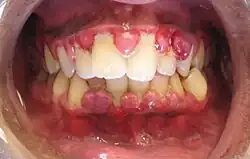

Eine Gingivahyperplasie (von lat. Gingiva „Zahnfleisch“ und neulateinisch hyperplasia „übermäßige Zellbildung“, auch Gingivahypertrophie) ist eine Zahnfleischwucherung. Die Bezeichnung ist unpräzise, da der Begriff der Hyperplasie sich auf eine erhöhte Anzahl von Zellen bezieht und eine Hypertrophie auf Erhöhung der Größe der einzelnen Zellen. Beides lässt sich nur histologisch feststellen.

Klinisches Erscheinungsbild

Die Stärke der Ausprägung ist unterschiedlich. Sie kann am gesamten Zahnfleisch oder lokal begrenzt im Bereich einzelner Zähne auftreten. Häufig sind anfangs die Interdentalpapillen betroffen und es sind Blutungserscheinungen einzelner oder aller Papillen zu beobachten. Östrogen- bzw. Gestagen-induzierte Zahnfleischwucherungen sind beispielsweise meist stärker ausgeprägt als die Phenytoin-verursachten.[4]